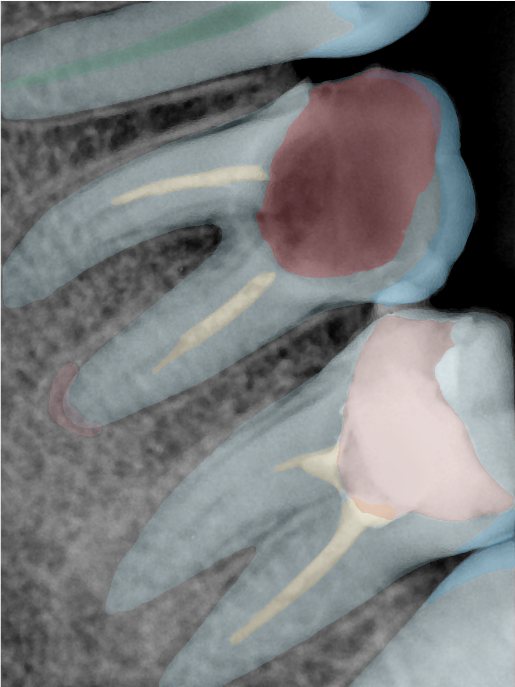

CR/DR 牙齿分割阶段记录

当前进展

- 完成了 CR/DR 牙齿相关分割训练

- 当前结果已经达到阶段预期,但仍有细节问题需要继续处理

相关测试

遇到的问题

- 训练过程中出现过 mask 下移问题

- 部分结果会出现 box 填充异常

- mask 边缘仍然有比较明显的锯齿感

第二版算法问题测试

| 第一版 | 第二版 | 是否解决 | |

|---|---|---|---|

![]() | ![]() ![]() 边角识别有问题 龋齿识别不全 牙髓识别不全 | ![]() | 解决 |

![]() | ![]() 边角识别有问题 识别信息有误 自查(牙冠识别不全) | ![]() | 解决 |

![]() | ![]() ![]() 边角识别有误 大范围填充识别遗漏 | ![]() | 解决 |

![]() | ![]() 识别信息不全 | ![]() | 解决 |

![]() | ![]() ![]() 边角问题 牙胶识别不全 牙冠识别不全 | ![]() | 解决 |

![]() 换图片 | ![]() | ![]() 牙冠部分稍微白了一些就识别成小范围修补,部分判断异常 | 部分解决,修复类略敏感,牙冠部分稍微白了一些就识别成小范围修补,部分判断异常。 |

![]() | ![]() ![]() 牙冠识别不全 牙髓不全 根尖炎龋齿识别有误 | ![]() | 解决 |

![]() | ![]() | ![]() | 解决 |

![]() 换图片 | ![]() | ![]() | 解决 |

![]() | ![]() 牙冠识别有误 | ![]() | 解决 |

![]() 换图片 | ![]() ![]() 边角识别有误 | ![]() 修复类敏感 | 部分解决,图像过白,导致修复类判断异常。 |

![]() 换图片 | ![]() 牙冠识别不全 | ![]() 修复类敏感 | 部分解决,图像过白,导致修复类判断异常 |

结论:修复类出现了不鲁棒的情况,后续需要加入轮廓的扩充数据进行增强。